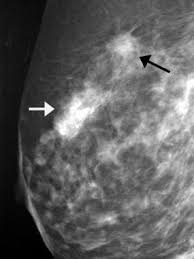

Did not respond to antibiotic and was referred for biopsy. Inflammatory breast cancer is often misdiagnosed because it is so rare, and is difficult to treat because it is particularly aggressive. What does breast cancer look like on a mammogram? However, inflammatory breast cancers are more likely to show solid mass lesions. My last breast ultrasound was december. As these inflammatory breast cancer picture shows, the texture of the breast may change and appear to look dimpled or ridged, like an orange peel. The woman who has inflammatory breast cancer has breast cancer that's red and inflamed, with an angry look to the breast cancer, he says. The problem is that inflammatory breast cancer can look very much like mastitis early on, and is often diagnosed only after a woman has been treated first for mastitis (often with no improvement in symptoms). What does breast cancer look like? I need some knowledge about ibc. These tubes, which are hollow, allow lymph fluid to drain out of the breast. I have inflammatory breast cancer which was firstly diagnosed as mastitis in jan 09. Women or men who develop any of the inflammatory breast cancer early signs should seek medical care immediately to ensure timely treatment.

The woman who has inflammatory breast cancer has breast cancer that's red and inflamed, with an angry look to the breast cancer, he says. What does breast cancer look like? Googled and freaking out about ibc. The problem is that inflammatory breast cancer can look very much like mastitis early on, and is often diagnosed only after a woman has been treated first for mastitis (often with no improvement in symptoms). Mammogram imaging may show skin thickening, but often there is no distinct mass found on physical examination or …

Most inflammatory breast cancers are invasive ductal carcinomas, which means. Inflammatory breast cancer accounts for between 1% and 5% of breast cancers and women do not usually have a lump and it doesn't usually. There is a pink area about the size of a quarter on the outside of my breast now for about a week with no change. Finding breast lumps and seeing change in the size and shape. Other ultrasound findings that suggest breast cancer include: This is referred to as peau d'orange, which is french for orange skin and it is caused by cancer cells blocking the lymph vessels beneath the skin, which have formed into ridges or tiny lumps. That indicates that the lesion likely contains a variety of elements, which may or may not indicate breast cancer. It often does not cause a breast lump, and it might not show up on a mammogram. In view of those symptoms often occur, and errors in diagnosis of patients treated for inflammatory diseases, that happen to be named and are known as these forms breast cancer. Ibc doesn't look like a typical breast cancer. This is a particularly aggressive cancer and i had chemo;bilateral mastectomy and radiotherapy ending at end of oct 09. I have inflammatory breast cancer which was firstly diagnosed as mastitis in jan 09. Learn more about ibc including the warning signs, diagnosis.